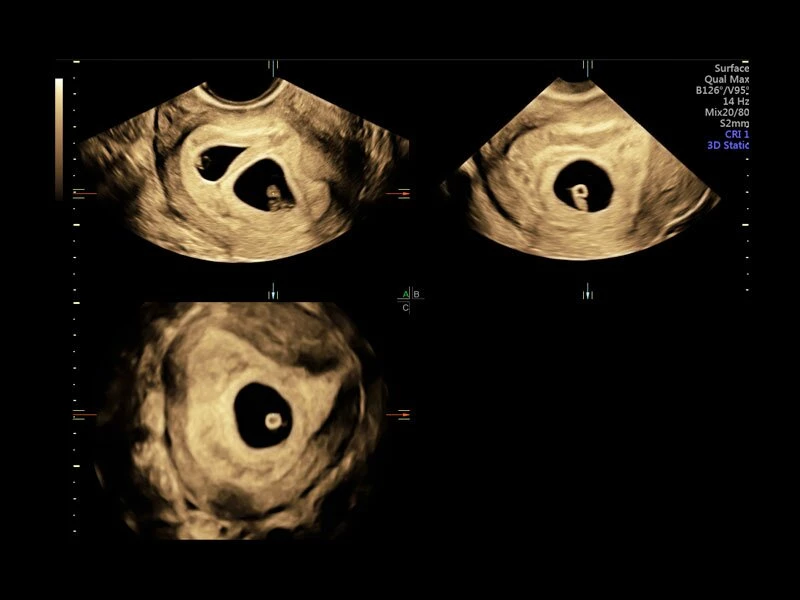

Объемное сканирование Voluson — 3D/4D вашей мечты

Объемное УЗИ на Voluson E10 — это не просто потрясающе красивая картинка, это ценный инструмент получения дополнительной информации при обследовании женщин.

Voluson E10 поддерживает инновационные технологии формирования изображений — HDlive Silhouette и HDlive Flow, которые позволяют увидеть мельчайшие детали. Алгоритм SonoRenderlive упрощает рабочий процесс и дает возможность реконструировать изображение поверхностей, определяя область перехода между тканью и жидкостью.

Инновационная технология визуализации HDlive обеспечивает получение реалистических изображений за счет эффекта объемного зрения, повышая достоверность клинической оценки. Теперь режим HDlive дополняют две новые функции:

- Технология HDlive Silhouette — задает разный уровень прозрачности, помогая выявлять контуры внутренних структур и точнее оценивать состояние плода в первом триместре.

- Усовершенствованный режим объемной визуализации с контрастированием (Volume Contrast Imaging, VCI) и опция OmniView

- Повышает контрастное разрешение и улучшает визуализацию области интереса в любой плоскости сечения, даже при исследовании структур неправильной формы.